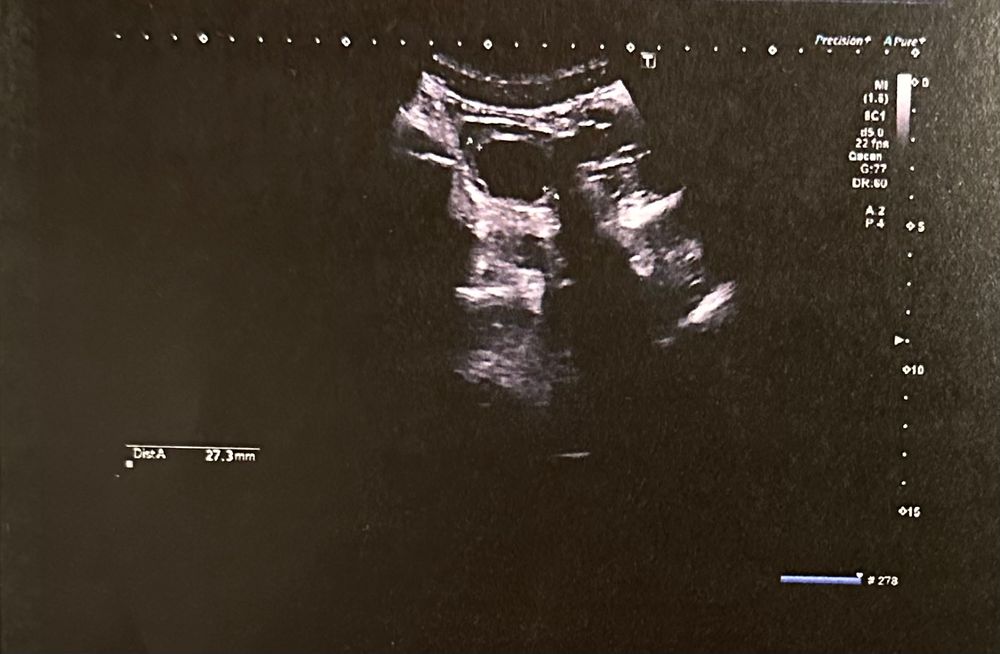

ФолликулометрияДевочки, подскажите пожалуйста, это желтое тело или что это ? У меня первый цикл планирования, пытаюсь разобраться

мы заграницей, толком на узи ничего не объяснили, сказали такое бывает из-за овуляции , что это конкретно не сказали. 29.2 на 27.3 мм